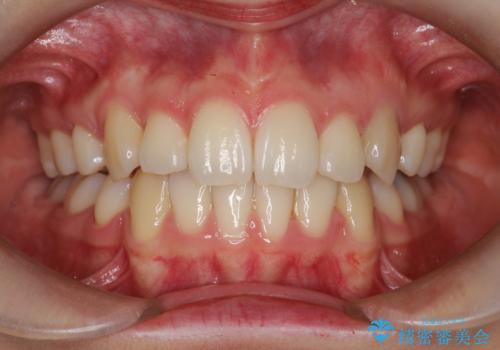

- 八重歯と前歯のガタガタを主訴に来院されました。

歯並びがコンプレックスで歯を見せて笑うことができなかったとのことですが、歯並びがよくなり、口元を気にせずに笑えるようになったと喜んでいただきました。